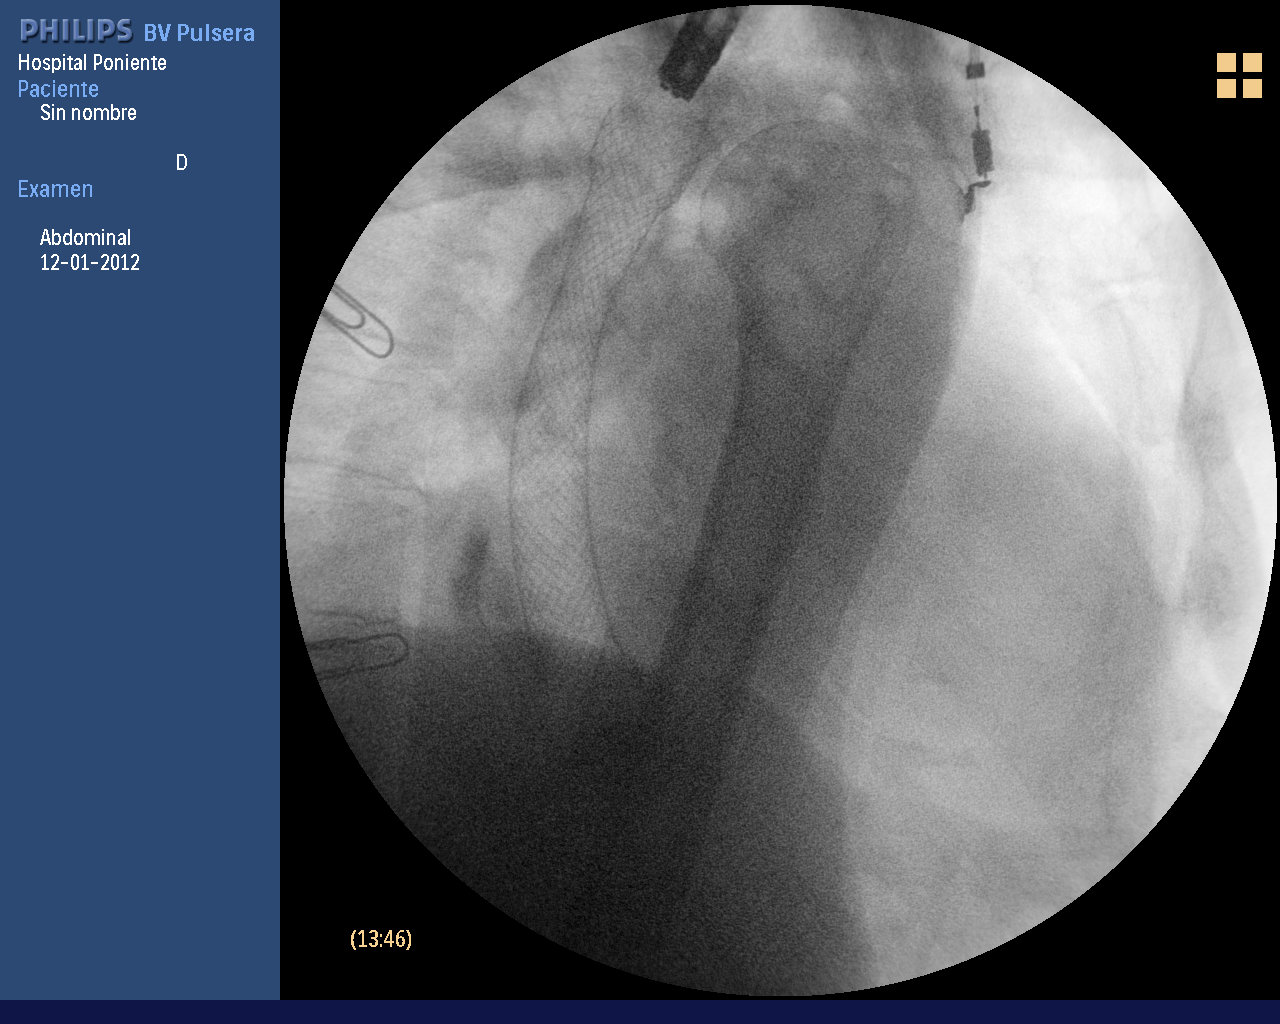

Paciente de 78 años de edad, fumador y bebedor importante, que ingresa en el hospital por HDA (vómitos hemáticos con restos de sangre fresca), pérdida de peso importante y disfagia lentamente progresiva en el último mes. Analíticamente se aprecia una ligera anemia normocítica (Hb 9.7 gr/dl). En la gastroscopia urgente realizada se observó una masa excrecente de unos 2.5 cm a 29 cm de la arcada dentaria que ocupa la totalidad de la luz esofágica, estenosándola e impidiendo el paso del gastroscopio. El estudio histológico de las biospias demostraron la presencia de un carcinoma espinocelular. El TAC toraco abdominal evidenció un engrosamiento transmural de todas las capas del esófago a nivel medio-distal, con varias adenopatías > 2 cm en el tronco celíaco. Se catalogó la lesión como carcinoma esofágico de estirpe espinocelular (escamoso o epidermoide) estadio T4. Tras valoración conjunta con cirugía y oncología, se decide únicamente paliación con prótesis esofágica. Se decide colocar ésta, parcialmente recubierta, de unos 12 cm de longitud, sin complicaciones inmediatas, usando el método conjunto de control fluoroscópico y endoscópico.

Existen muchos métodos para colocar una prótesis esofágica. Nosotros pensamos que toda estrategia que ayude en la correcta elección de la longitud  de la prótesis y que mejore el ajuste de ésta es bienvenida. En este caso, con la disponibilidad de un gastroscopio de fino calibre (8 mm) y mayor flexibilidad, se ha podido franquear la estenosis y medir la longitud de ésta, sin tener que dilatarla. Posteriormente se ha hecho un marcaje del extremo proximal de la estenosis con contraste hidrosoluble. El problema de la inyección de contraste es que se dispersa mucho por la submucosa y puede dar errores en la medición. El lipiodol es mejor por difundirse menos. Usando como referencia el extremo del endoscopio, se colocaron 2 clips externos. Bajo control conjunto con fluoroscopia y endoscópico (ajuste proximal), se ajustan los extremos de la prótesis de forma mas eficaz.